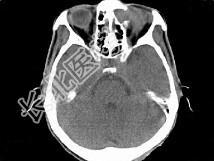

- 单项选择题男,53岁, 近两年来渐进性头痛,伴左眼球外突, 并向前下方移位,CT检查如图, 最可能诊断为 ( )